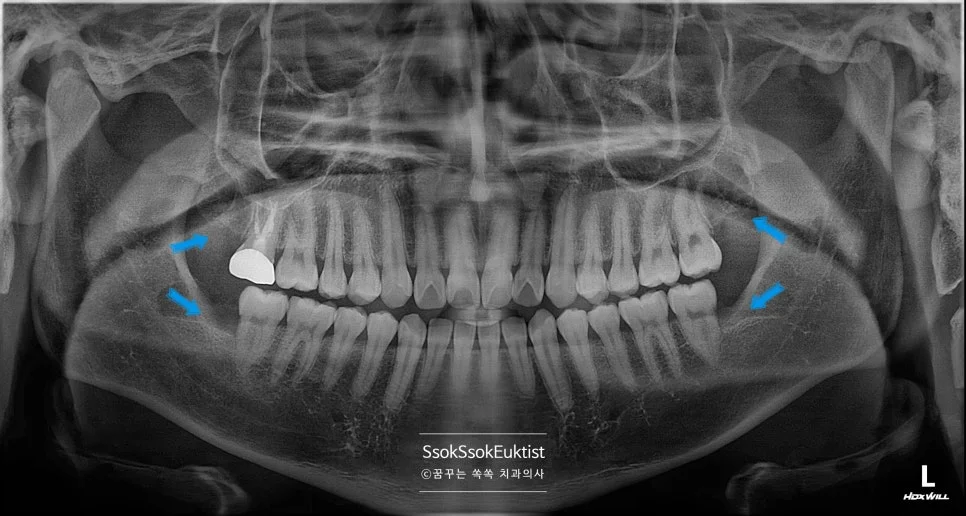

매복 사랑니 파노라마 진단 사진

그런데 파노라마 사진을 촬영한 후 간단한 검진을 시행하니 사랑니가 4개 모두 존재합니다.

파노라마 방사선 사랑니 4개 위치

파노라마 방사선 사진 — 파란 화살표로 4개의 사랑니 위치를 표시